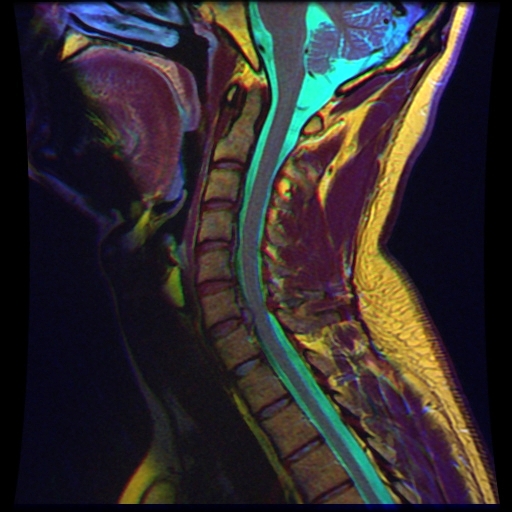

경추(C6-C7)의 추간판탈출증

경추의 정상적인 상황(좌)과 경추 추간판 탈출증(우)